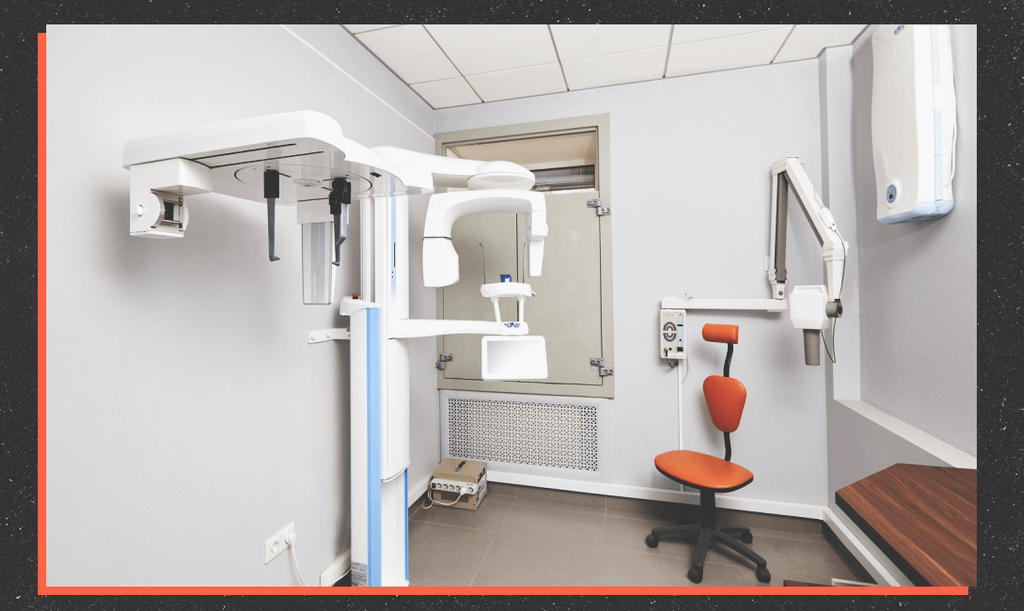

Помимо аутотрансплантации в PerfectSmile проводят все инновационные процедуры: от диагностики скрытого кариеса и лечения его под седацией до профессиональной гигиены полости рта на японском аппарате AirFlow и отбеливания зубов по системе Zoom4.

В каждом кабинете клиники есть стоматологический микроскоп для детального обследования. С его помощью удаётся увеличить место осмотра в 30 раз и выявить любую зубную болезнь ещё на стадии развития. Собственная зуботехническая лаборатория позволяет максимально быстро изготавливать различные индивидуальные конструкции – коронки, виниры, протезы и ортодонтические аппараты.